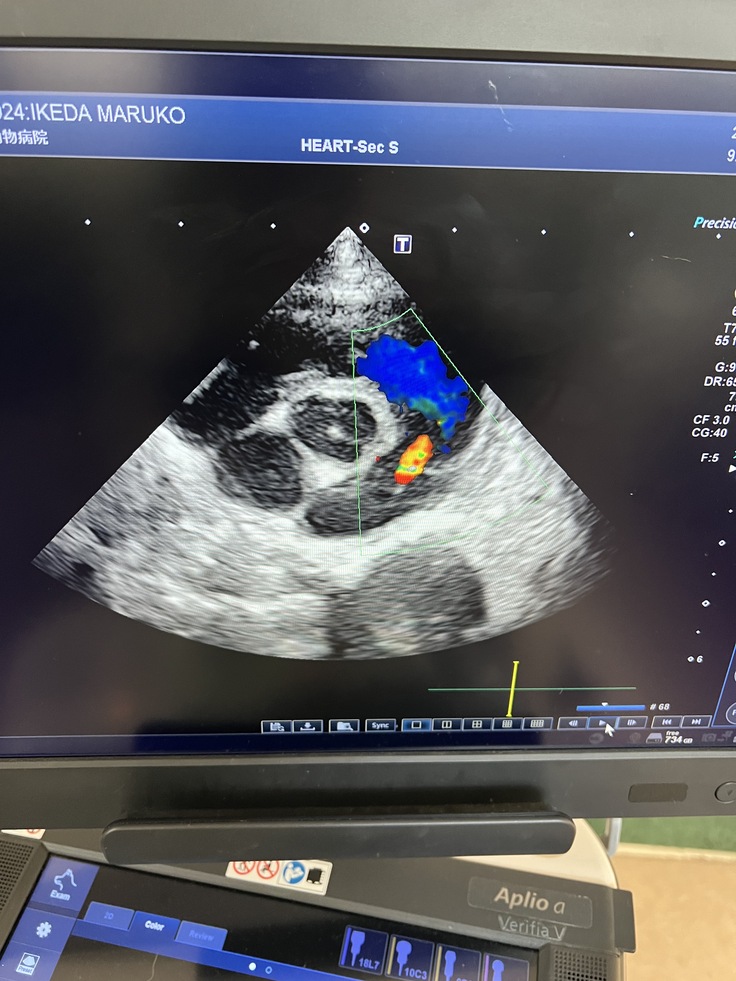

↑まる子のエコー